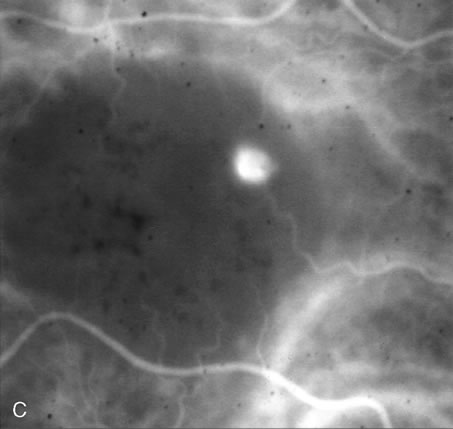

Fig. 34. Full-thickness and partial macular holes. A. There is a discrete hole in the central macula. Hyperfluorescence reflects choriocapillaris leakage that is normally partially blocked by retinal pigment epithelium. B. There is partial blockage of the choroidal hyperfluorescence, but subtle hyperfluorescence is visible. (Courtesy of Dr. Peter Judson.)